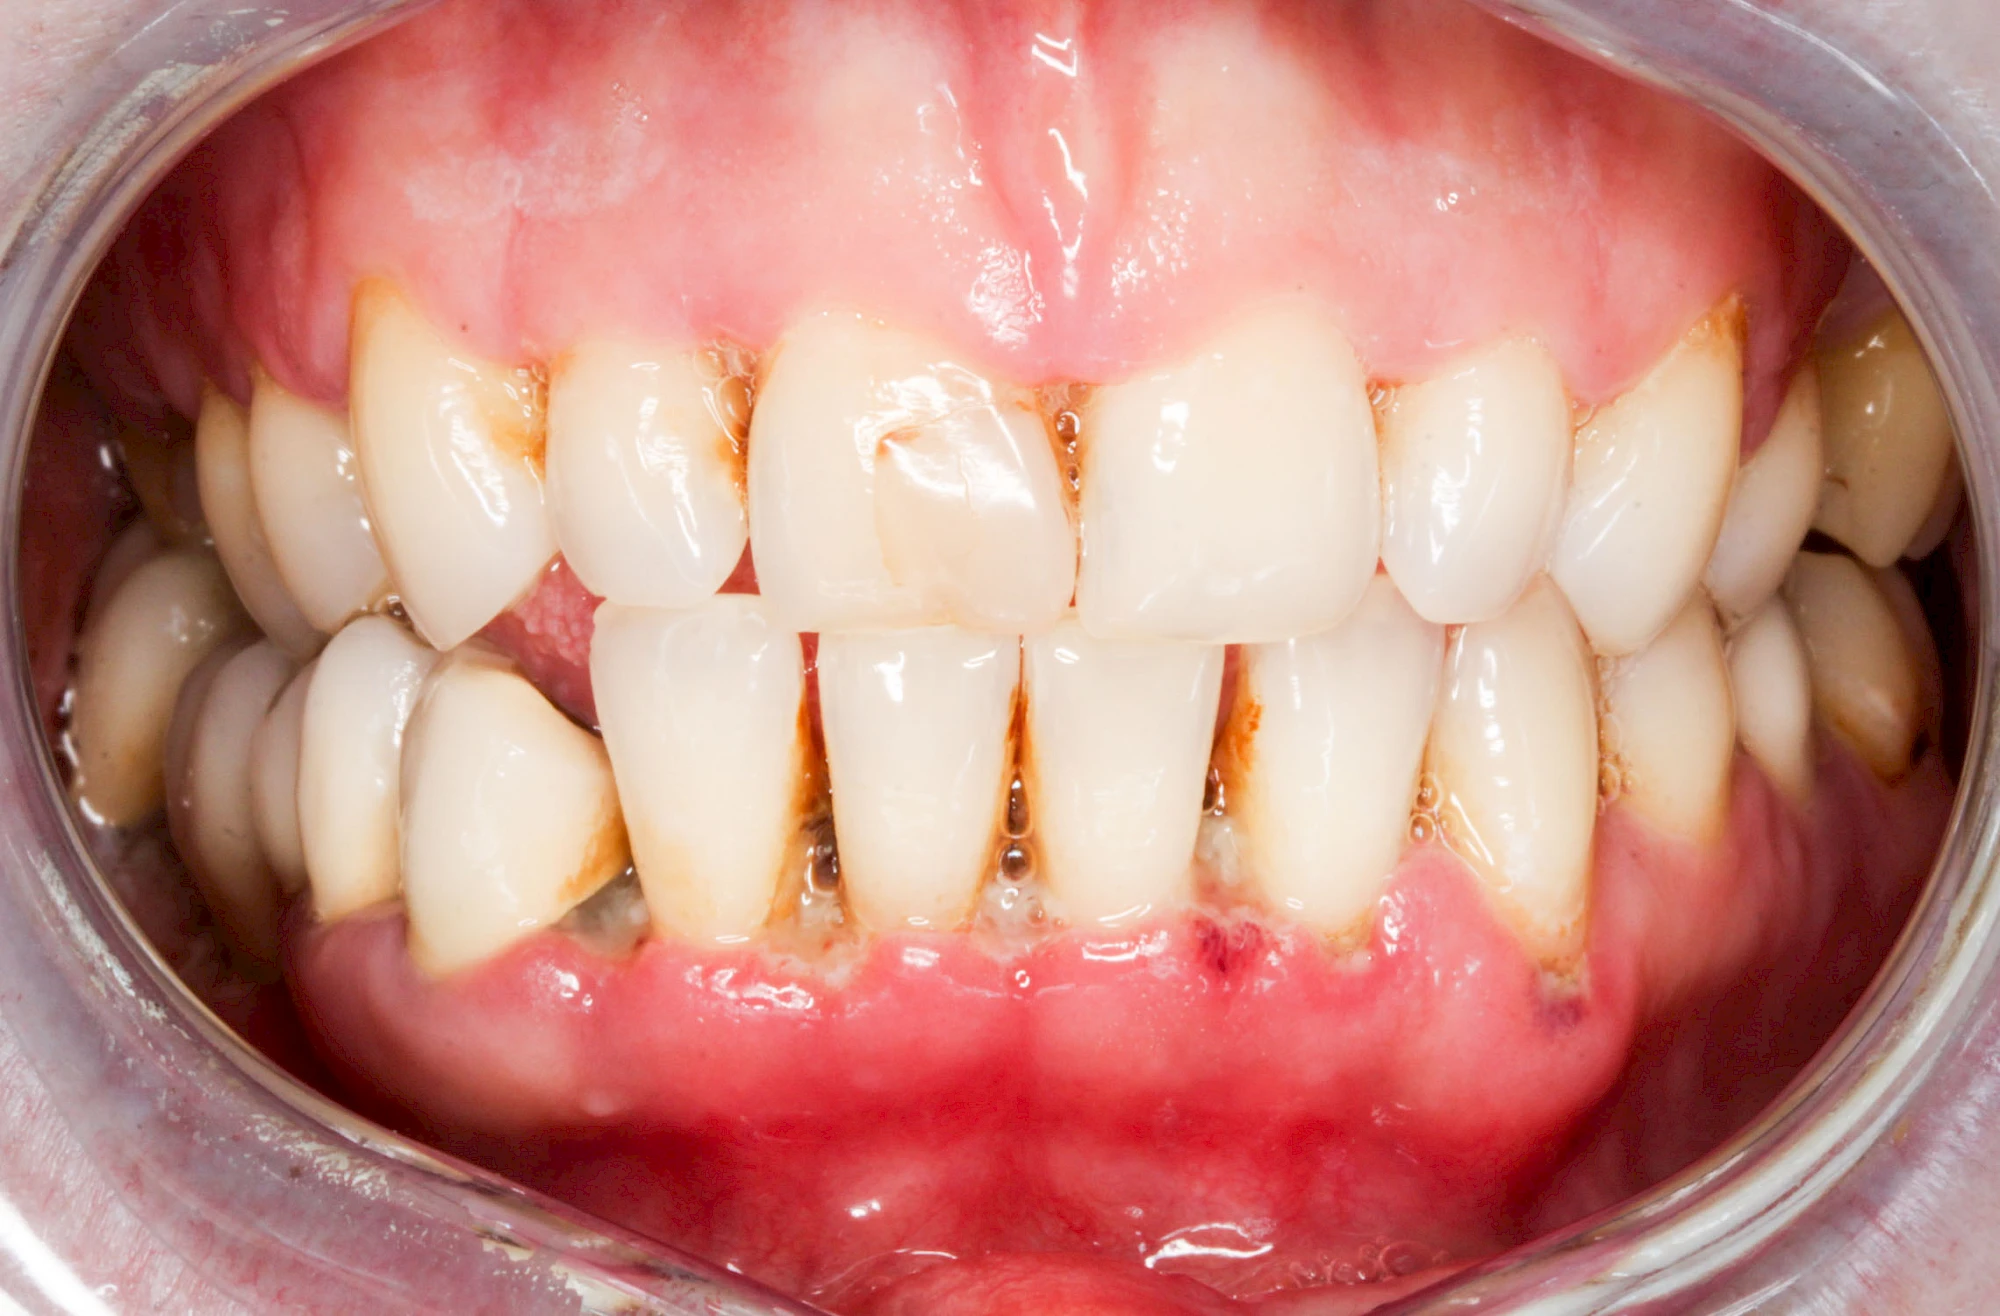

Bakterien in den Zahnbelägen greifen neben den Zähnen auch das Zahnfleisch (Gingiva) und den gesamten Zahnhalteapparat (Parodont) an. Der Körper reagiert mit einer Entzündung, sichtbar als Rötung und Schwellung. Meist blutet das Zahnfleisch z .B. beim Essen oder auch beim Putzen der Zähne.

Ist zunächst nur das Zahnfleisch von der Entzündung betroffen, spricht man von Gingivitis. Später, wenn auch der Knochen um die Zähne herum entzündet ist, spricht man von einer Parodontitis. Bei der Parodontitis wird der Knochen nach und nach abgebaut und das Zahnfleisch zieht sich zurück. Die Zahnhälse und Zahnwurzeloberflächen liegen mehr und mehr frei. Die Zähne werden zunehmend lockerer und fallen schließlich aus.

Bei Schwellung, Rötung oder Blutung des Zahnfleisches sollte neben der Intensivierung und Optimierung der Mundhyiene der Zahnarzt kontaktiert werden.